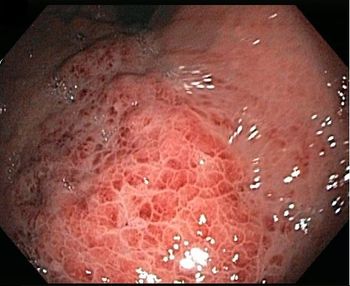

A 61-year-old man with arthritis and an 80-pack-year smoking history presented with fever, dyspnea, and productive cough of a week’s duration that did not respond to outpatient treatment with levofloxacin.